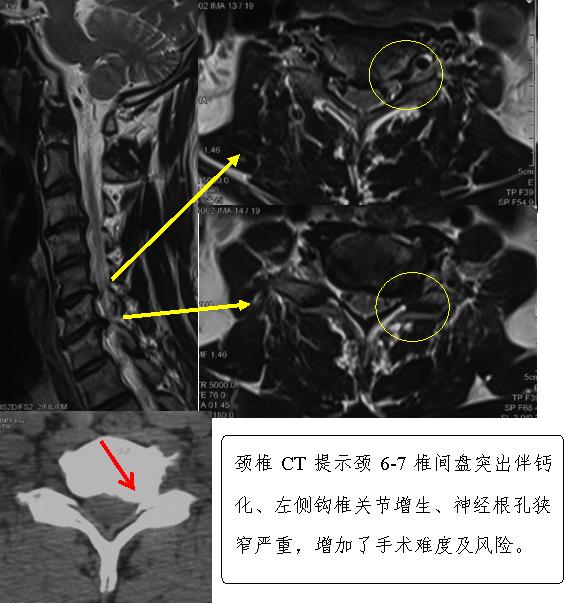

杜主任在详细询问了患者的病史,经过仔细查体,结合影像学资料,初步诊断患者为“颈椎间盘突出症(C5-7)”。影像学资料显示,患者颈5/6及颈6/7两个节段的椎间盘向左后突出,同时伴有左侧钩椎关节增生,神经根孔狭窄,严重卡压左侧神经根,这些病理改变在椎管内形成一个个“老茧”,不仅记录了这位贝斯手几十年为追求艺术完美而付出的辛劳。同时,“老茧”的存在所引发肢体各种症状也成为影响他继续演奏心爱乐器的罪魁祸首(见下图)。

结合影像资料和患者职业特点,医生认为,保守治疗恐怕已经不能解决患者问题,手术治疗应该是最佳选择。杜主任带领科室人员对患者病情反复进行讨论,经慎重考虑,决定由他带领陈宇飞、张振宇、刘悦及许砾思医生为患者实施“前路颈5-7椎间盘切除减压、植骨融合内固定术”。手术从患者颈前右侧沿皮纹切开一个4cm的切口,在切除颈5-6,颈6-7退变椎间盘的同时,用超声骨刀切除颈6-7左侧增生的钩椎关节并扩大左侧的神经根孔。随着一个个“老茧”的剔除,患者神经压迫症状迅速得到缓解,达到了美观、微创的效果(见下图)。手术历时约2小时,出血量极其微少约2毫升左右。